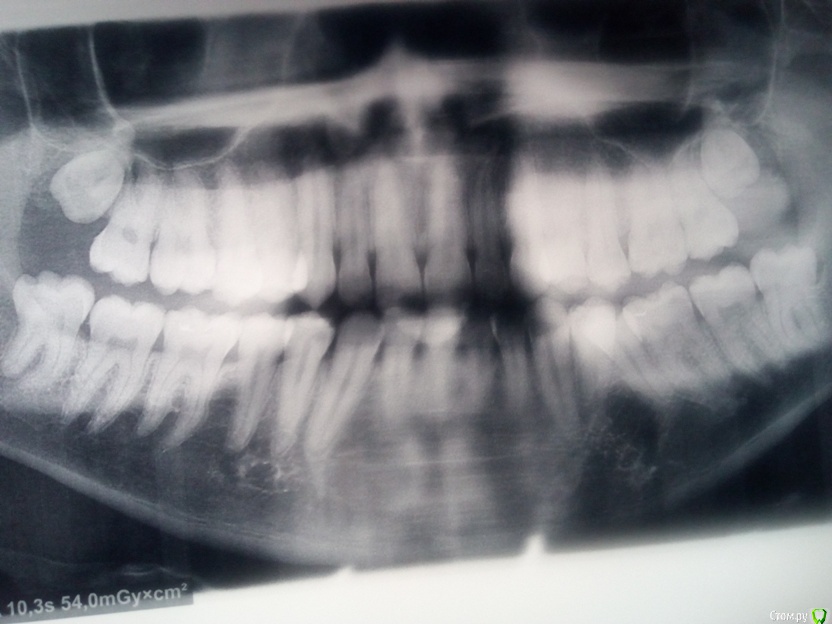

Здравствуйте. Предлагают удалять этот зуб. Я так понимаю нужно соглашаться. Не могли бы дать прогноз встанут ли нормально остальные после удаления? Восьмерки есть. 27 лет.